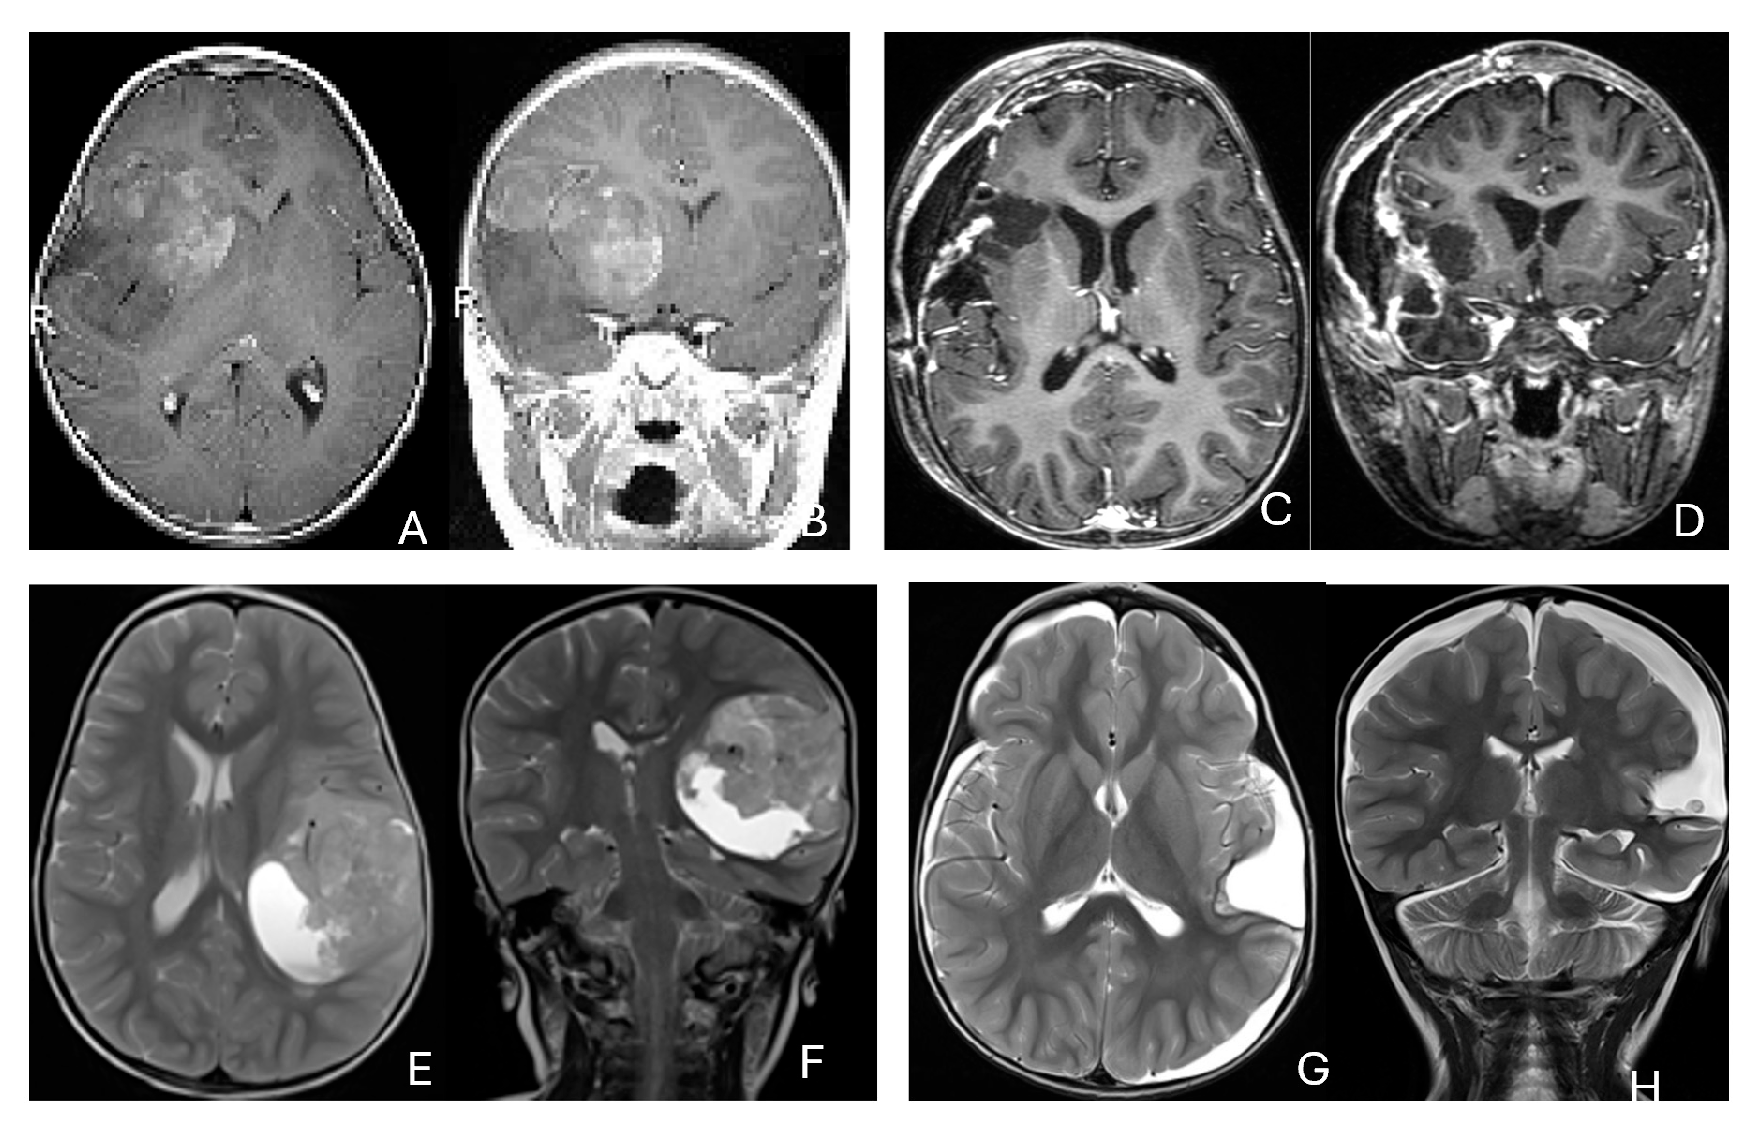

Figure 2.

Multi-lobe ATRT. (A–D): A 3-year-old boy with a heterogeneous frontotemporal ATRT with encasement of Sylvian vessels on MR images ((A), axial; (B), coronal). Intraoperatively, the tumor replaced both the frontal and temporal opercula, extended to the anterior, and displaced/encased branches of the middle cerebral artery. Postoperative MR images after resection ((C), axial; (D), coronal) confirm multilobe involvements. (E–H): of a 30-month-old boy with a temporoparietal cystic ATRT crossing the Sylvian fissure shown on T2-weighted MR images ((E), axial; (F), coronal). Correlative intraoperative findings and imaging demonstrated the tumor extending from the temporal lobe into the posterior frontal lobe across the Sylvian fissure and encasing middle cerebral artery branch. Post-resection MR images ((G), axial; (H), coronal) show a resection cavity spanning the temporal and posterior frontal opercula.

Three tumors were predominantly located within the ventricle, two within the lateral ventricle and another within the third ventricle (Figure 4). None appeared to arise from the choroid plexus or as pedunculated lesions from the ependymal layer; rather, operative and imaging features supported a paraventricular origin because of diffuse attachment to the ventricular wall. Two large hemorrhagic hemispheric tumors extended into the lateral ventricle. These paraventricular ATRT extends into the lateral ventricle (Figure 5).

Figure 4.

Intraventricular ATRT. (A–D): A 7-month-old boy with ATRT within the left lateral ventricle with associated hydrocephalus shown on MR images ((A), axial; (B), coronal; (C), sagittal). Note irregular peritumoral cysts and ependymal invasion which was confirmed at surgery. Postoperative MR image ((D), axial) shows a gross-total resection. The patient had a history of rhabdoid tumor predisposition syndrome. (E–H): A 34-month-old boy with MR images ((E), axial; (F), coronal; (G), sagittal) showing an intraventricular mass at the anterior horn based on the septum pellucidum. ATRT was originated at the junction of the septum pellucidum. Post-contrast MR ((H), axial) confirms resection. (I–L): Post-contrast MR images ((I), axial; (J), coronal; (K), sagittal) of a 3.5-year-old boy demonstrate a large, enhancing third ventricular ATRT with partial extension into the lateral ventricle. The lesion was removed via an interhemispheric transcallosal approach ((L), sagittal).

Figure 5.

Paraventricular ATRT with ventricular extension. (A–D): A 3-month-old girl who presented with emesis followed by acute decerebrate posturing. Post-contrast MR images ((A), axial; (B), coronal; (C), sagittal) reveal a large hemorrhagic mass in a deep centrencephalic location. Postoperative MR ((D), axial) shows a focal dilation of the lateral ventricle after subtotal resection of a parietal para-ventricular ATRT.